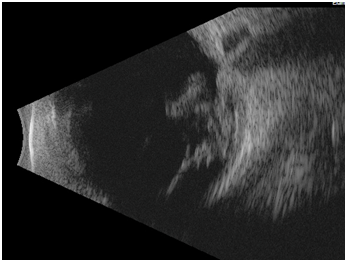

A 15-year-old healthy male presented with an ocular injury sustained while playing basketball. He described a finger poke incident with the contact made with the lower aspect of his right eye. Immediately following the injury, he described loss of vision of the right eye. On presentation to the emergency eye clinic 2 hours later, his visual acuity was no light perception in the right eye. A right relative afferent pupillary defect was present. A conjunctival tear and associated chemosis was present in the inferior bulbar conjunctiva. A micro-hyphaema with 2+ red cells was found in the anterior chamber but the cornea, lens and intraocular pressure were all normal. Examination of the posterior segment revealed localized vitreous haemorrhage arising from the disc. The disc itself appeared disorganized and recessed behind the globe with an obvious defect in the disc superiorly (Figure 1). Gentle palpation of the globe during fundus examination showed that some streaks of vitreous haemorrhage adjacent to the disc were mobile and could pass through the disc defect with gentle palpation and return into view on release of palpation. There was retinal pallor affecting the superior temporal and nasal aspects of the retina (Figure 2). A B-Scan ultrasound demonstrated alteration in the normal contour of the optic nerve/ globe junction and hypo echogenic area adjacent to the nerve (Figure 3). MRI of the brain and orbit showed disruption in the area of lamina cribrosa of the right eye (Figure 4). At 3 weeks following the injury, progressive dense vitreous haemorrhage prevented visualization of the posterior pole (Figure 5). Subsequent follow up after one month showed that the vitreous haemorhage disperse spontaneously, with persistent optic nerve disorganization and no improvement in vision.

Figure 3 B scan ultrasound demonstrating vitreous haemorrhage, altered optic nerve/globe junction and hypoechogeneic area posterior to globe.